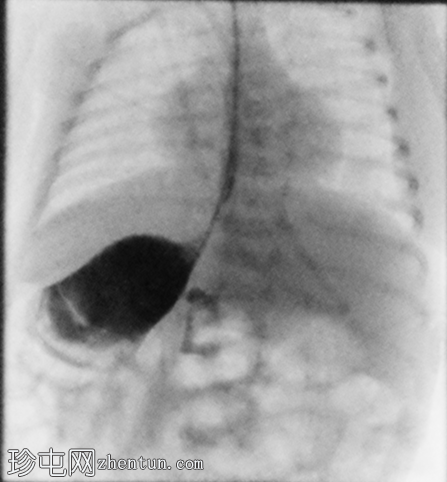

正位

定位片显示肠道气体分布无梗阻,经食管插管终止于右上腹。

胃位于右上腹。观察到轻度中段食管反流。造影剂在近端十二指肠的延迟通过量极少,这属于异常情况。